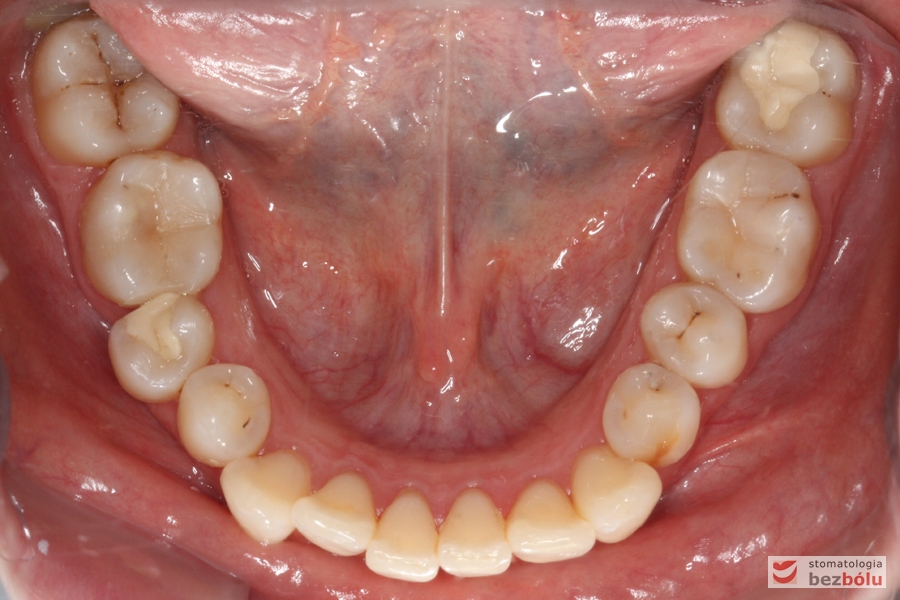

Pacjentka lat 26 zgłosiła się do gabinetu celem korekcji uśmiechu. Głównym zmartwieniem były problemy estetyczne, które znacznie wpływały na jakość życia pacjentki. Wykonano leczenie zachowawcze zębów oraz analizę cefalometryczną i analizę modeli diagnostycznych. Zaplanowano leczenie aktywne aparatem DAMON dla szczęki i żuchwy, które trwało 2 lata. Po fazie leczenia aktywnego rozpoczęto leczenie retencyjne z użyciem szyny tłoczonej dla szczęki i retainera stałego dla żuchwy.